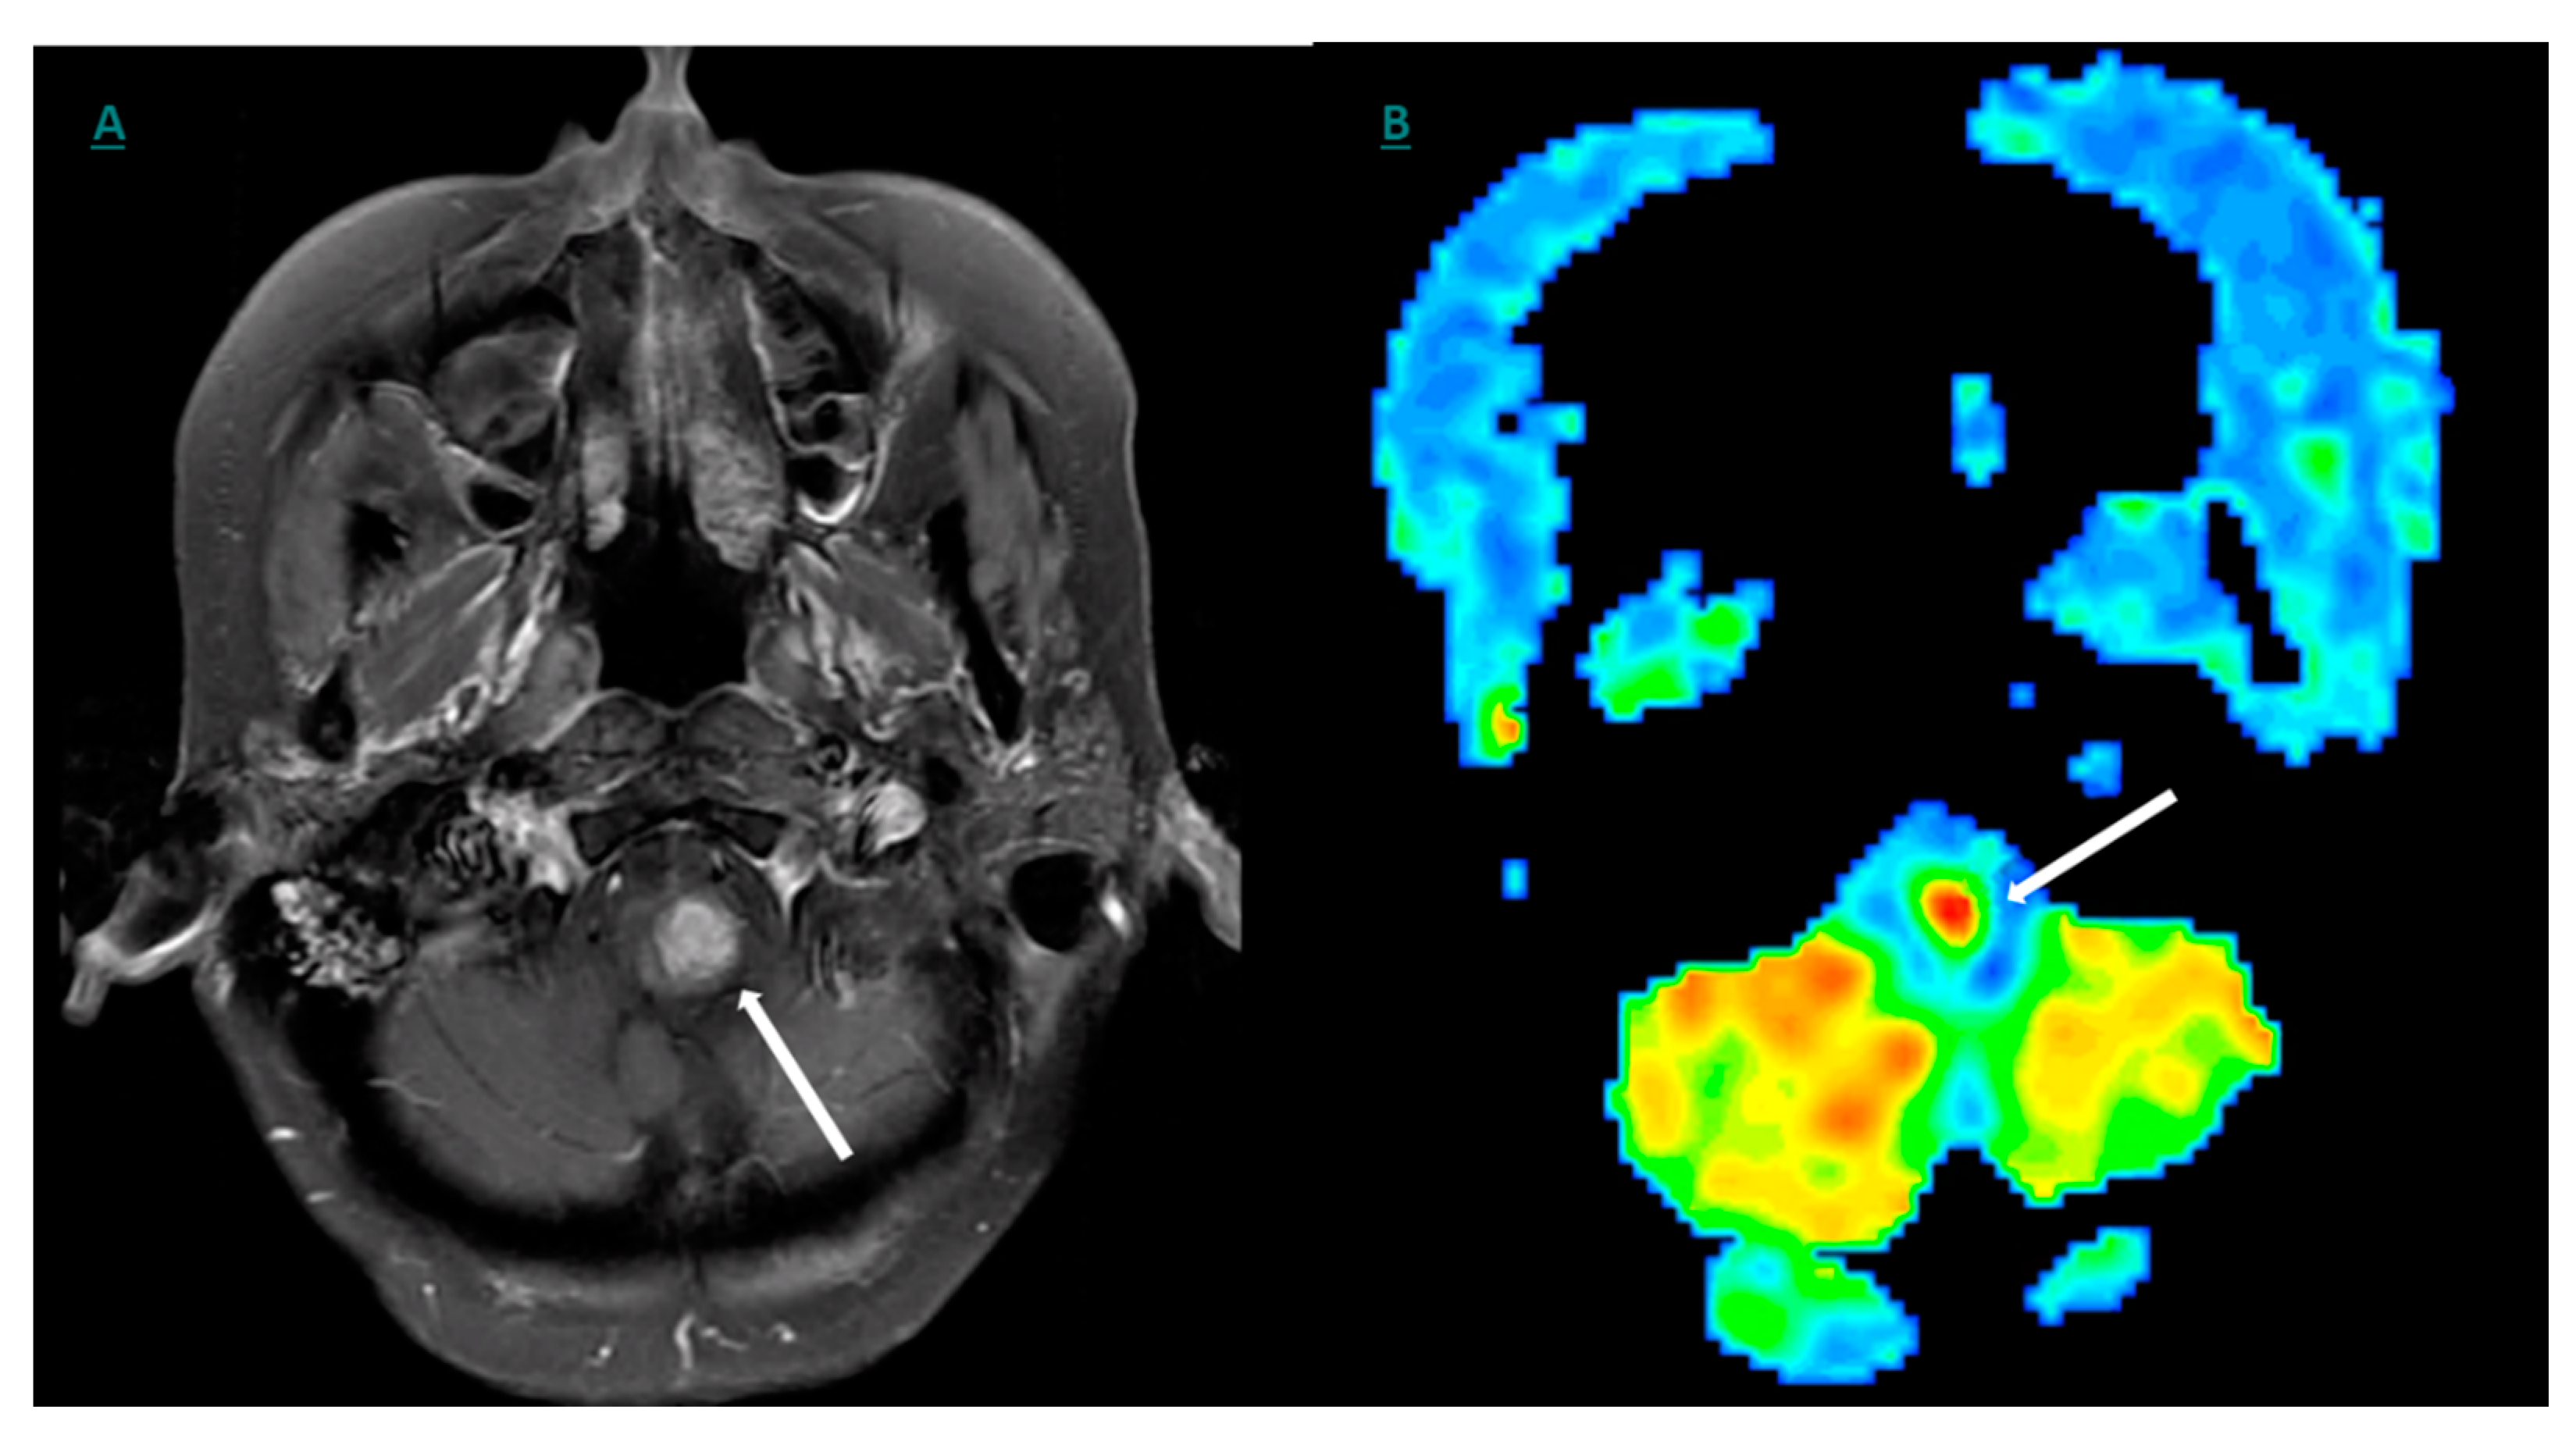

10. Positron Emission Tomography (PET) and Molecular Imaging

11. 18F-FDG- (Fluorine 18 Fluoro-Deoxy-Glucose)-Based Imaging